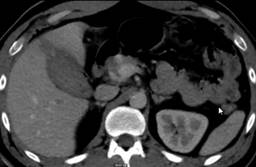

El paciente continúa sin datos de irritación peritoneal, sin abdomen agudo, aunque por datos de probable hemobilia, se solicita tomografía computarizada (TC) de abdomen a las 29 horas de evolución reportando: laceración hepática del segmento V grado I de la AAST, vesícula de 81 × 44 × 48 mm de contenido heterogéneo, descrita en la Figura 3.

Figura 3: Imagen de tomografía computarizada en la que se observan cambios en la densidad del contenido de la vesícula, aparentemente contenido hemático, escasa cantidad de líquido perivesicular.